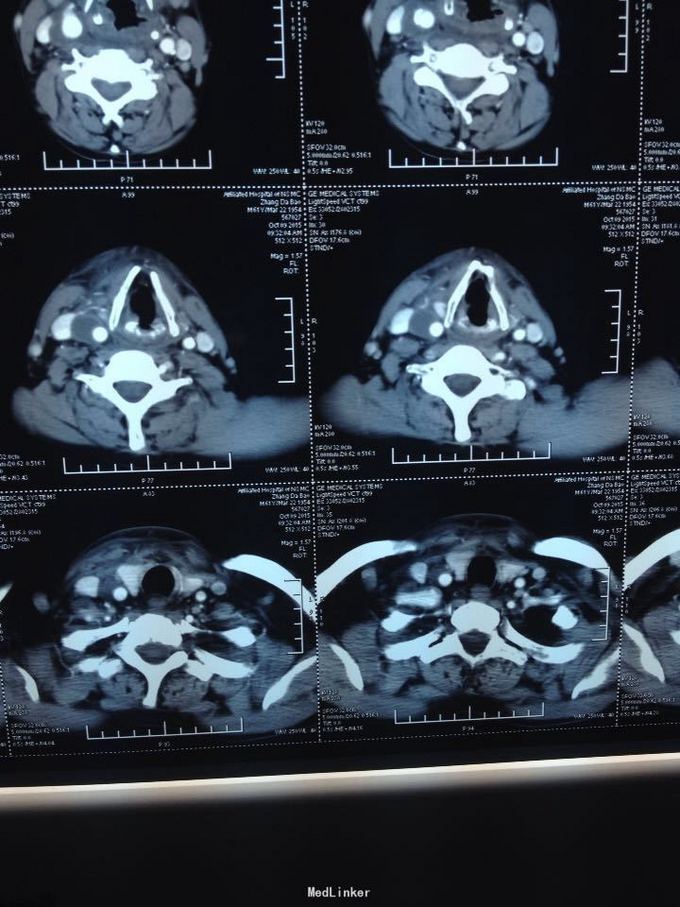

颈部多发脓肿。入院后完善相关检查,给予抗感染、对症支持治疗,并于急诊全麻下行颈部脓肿切开引流术,术中分离右侧颈动脉鞘,充分分离脓腔,充分引流。

颈部感染致脓肿多发是颈部感染的严重转归,而脓肿累及颈鞘时需要高度警惕,防止脓液腐蚀动脉血管,导致血管破溃大出血而致患者休克甚至死亡,需要充分告知患者及家属具体风险,手术中需要尽可能彻底分离脓腔,动脉周围脓肿需要谨慎分离。注意保护。